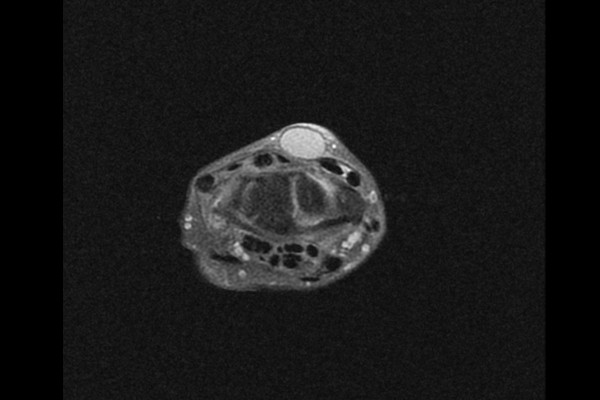

주변 신경과의 관계 및 신경의 이상유무를 확인하기 위해 촬영한 MRI 검사 결과, 명확하게 보이는 물혹, 결절종이 확인되었습니다.

다른 방향의 사진을 확인해보아도 물혹, 결절종이 확인되어 손목 물혹 결절종(Ganglion wrist dorsum)을 진단하였습니다.